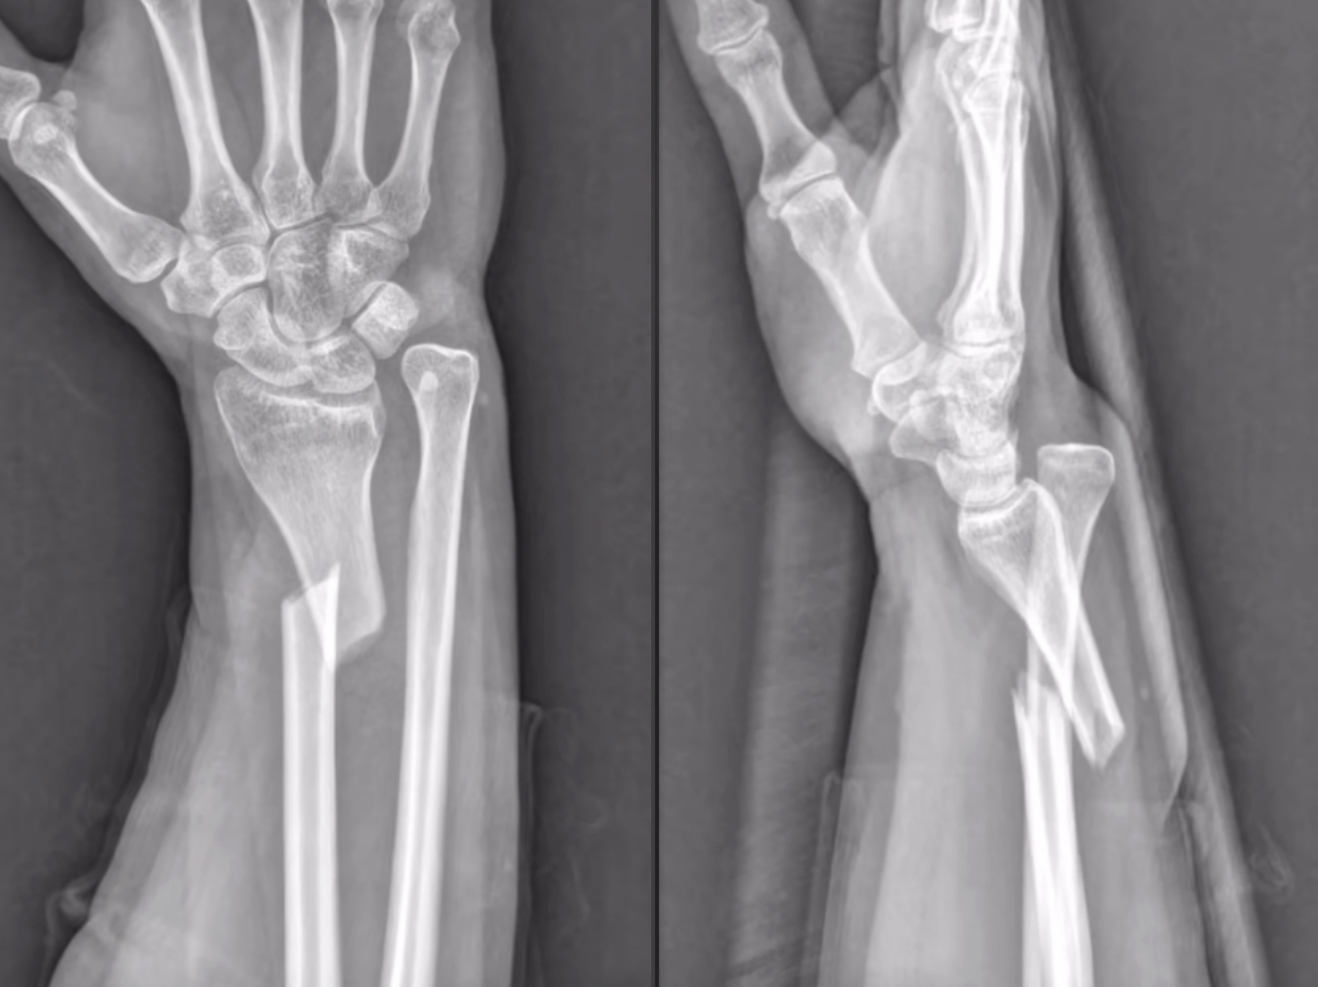

蓋氏骨折復(fù)位前 蓋氏骨折復(fù)位后